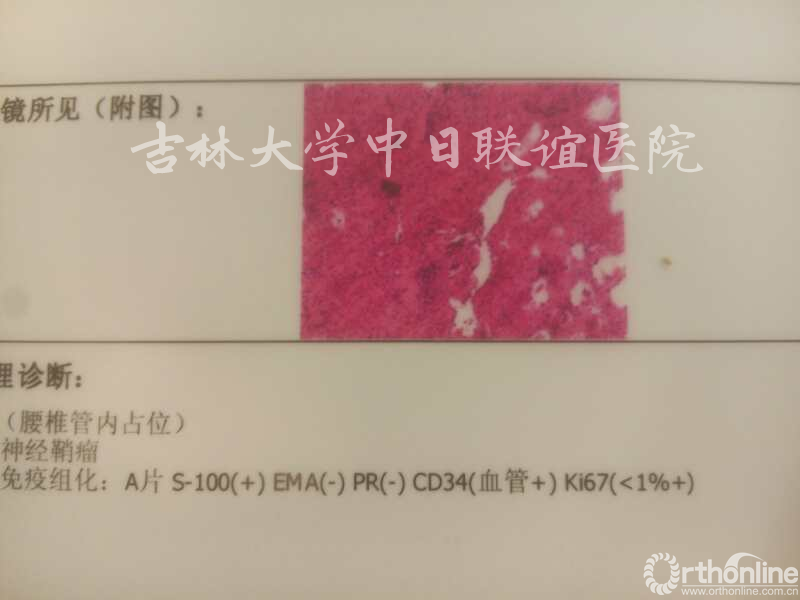

术后病理:

神经鞘瘤(Neurinoma)